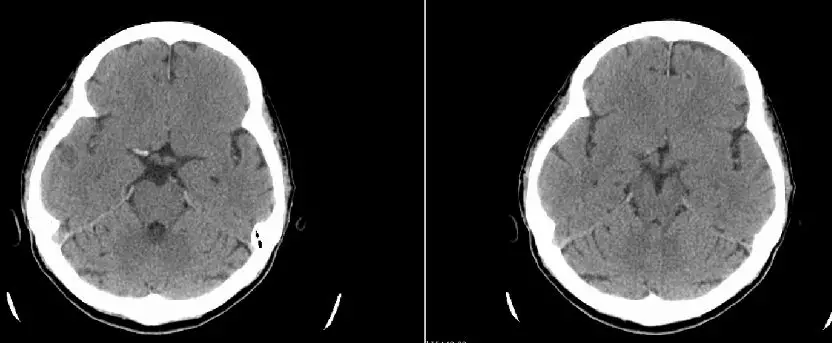

再次造影发现,整个颈内动脉(ICA)C段通畅,但眼动脉段以远依然闭塞。

8F指引导管联合6F Navien中间导管,通过中间导管造影,提示ICA眼动脉段以远未见显影

将导丝放置于病灶后,微导管放置到位,远端造影证实在血管腔内。置入6*30mm支架后,发现整个右侧MCA完全无显影。证实术前CT平扫高密度征的准确性,血栓负荷量比较大。

8F指引导管联合6F Navien中间导管,右侧MCA取栓:微导丝到位;Rebar27导管到位,冒烟证实于血管腔内;6*30mm支架放置MCA-M1段,MCA未见显影,ACA未见显影;表明血栓负荷非常大

造影后发现,右侧ACA部分再通,MCA仍闭塞。支架静置4分钟后造影提示显影更差。

双支架放置后造影提示,右侧ACA部分显影,MCA仍血管显影不佳(A),双支架放置4分钟后造影提示,右侧前循环显影更差(B)